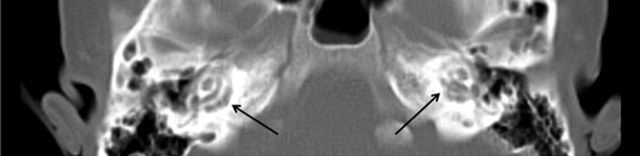

Figure 1

Axial CT-scan shows bilateral lucencies in the pericochlear bony otic capsule.

The CT imaging of the temporal bone in OI patients with hearing loss shows reduced density in the bony regions around the semicircular canals, the distal internal auditory canal and oval window. Involvement of the fissula ante fenestram, oval window and round window (fenestral structures) correlates to conductive hearing loss. On the other hand, the involvement of the cochlear turns, semi-circular circles and facial canal (retrofenestral structures) is linked to sensorineural hearing loss [7].